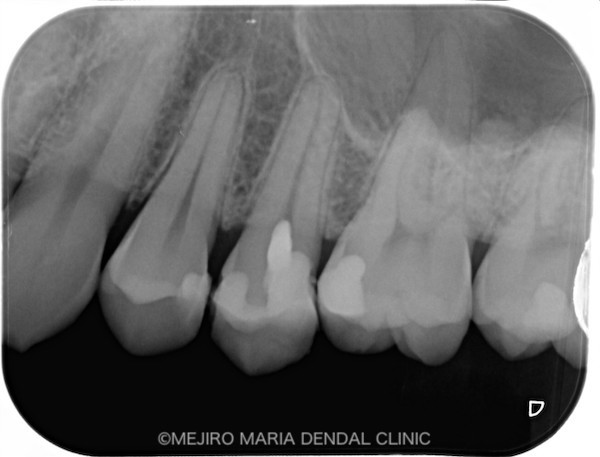

術後2週間経過した時点で、歯髄の反応が正常であることを確認しました。今後は、セラミックインレーを装着する予定です。

目白マリア歯科_【症例】生活歯髄断髄法(生活歯髄療法)による歯髄保存症例(精密根管治療)術前術後レントゲン画像